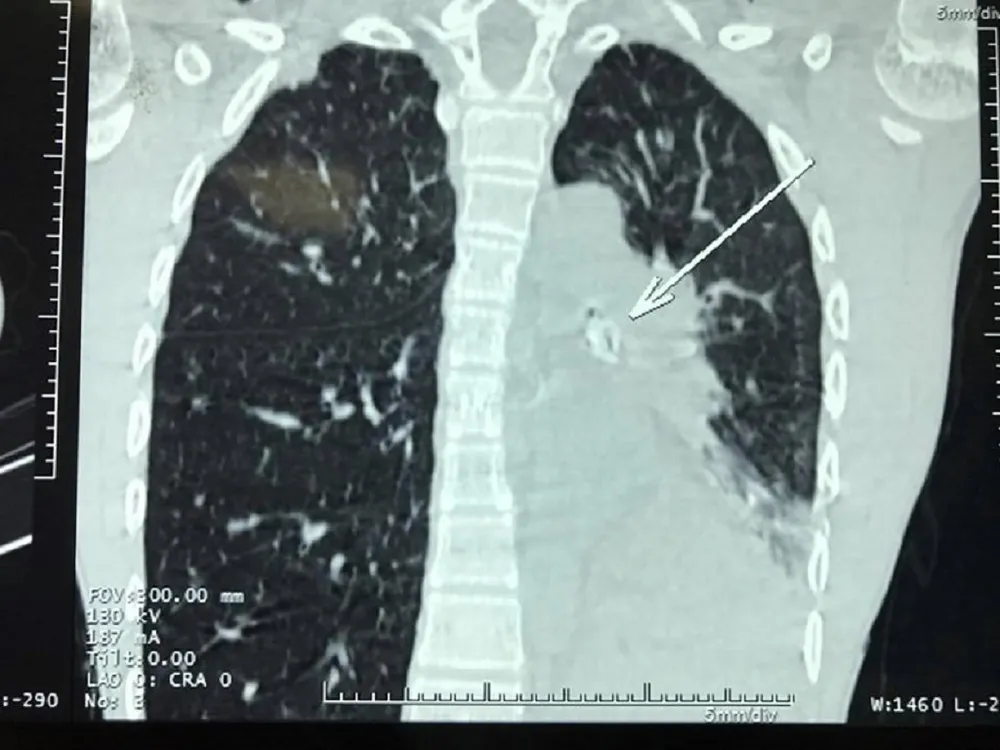

Vị trí hạt xí muội trong phế quản trái của bệnh nhi